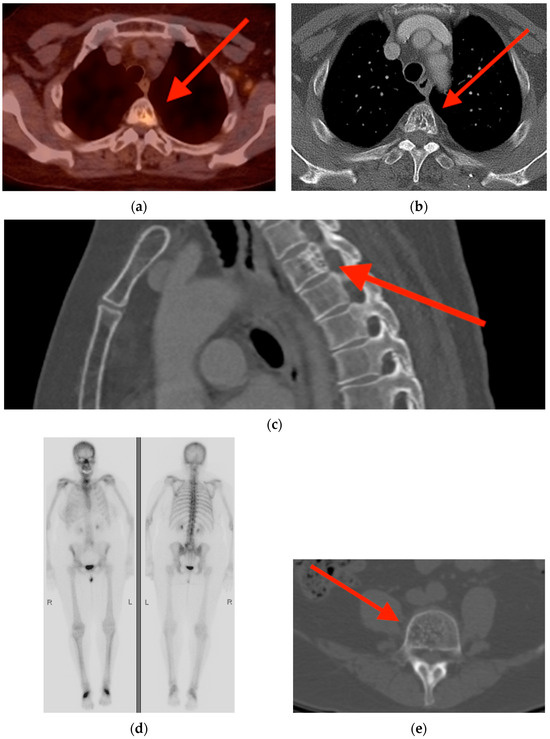

2.1. Fracture